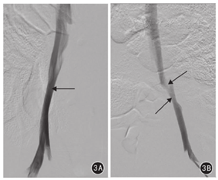

术后第30天实验组行髂静脉造影检查显示:右髂静脉通畅,左髂静脉可见明显狭窄(图3)。

实验组动物手术前左髂静脉直径为7.28~8.04(7.53±0.28)mm,术后第30天为3.72~5.02(4.39±0.48)mm,手术前后左髂静脉直径差值为2.32~3.88(3.14±0.57)mm,左髂静脉狭窄率为31.6%~51.1%(41.57%±6.85%),均成功建立了髂静脉狭窄模型;手术前后左髂静脉直径差异有统计学意义(t=13.575,P<0.05)。术后第30天,实验组动物髂静脉造影显示右髂静脉均通畅,左髂静脉可见明显狭窄;静脉壁组织病理学检查显示:对照组未见异常,实验组血管内膜增生狭窄;实验组左髂静脉内膜厚度为(209.82±26.26)μm,大于对照组的(37.67±6.84)μm,差异有统计学意义(t=15.539,P<0.05)。